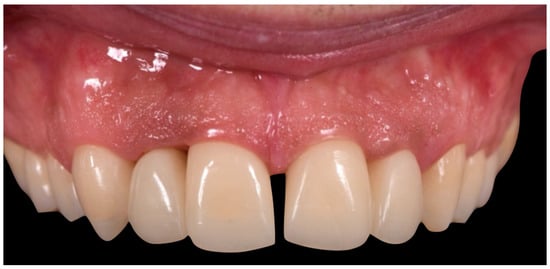

The second provisional restorations (Figure 12) were luted using zinc phosphate cement (Harvard) and mixed with petroleum jelly to facilitate later removal. At this stage, the interincisal diastema was closed. During the second provisional phase, tooth 1.2 developed symptoms of thermal sensitivity and mild pain, necessitating endodontic treatment.

Figure 12. Second provisional restoration.